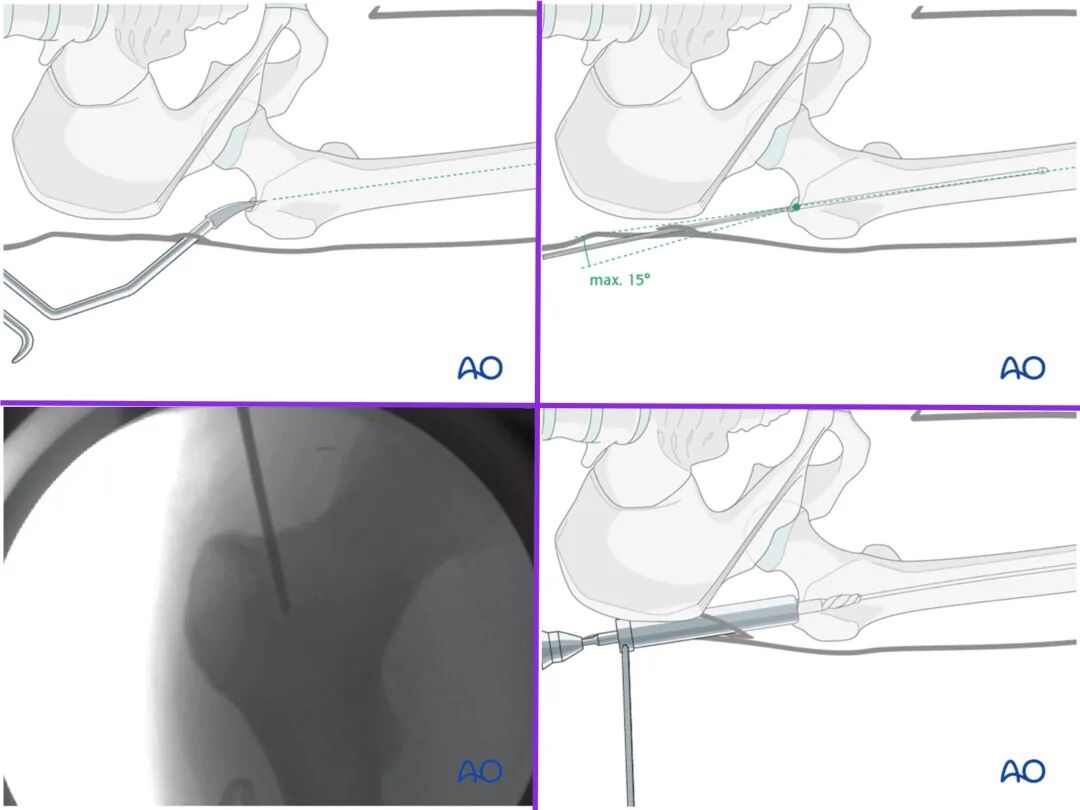

干货分享,AO梨状窝进针操作技巧